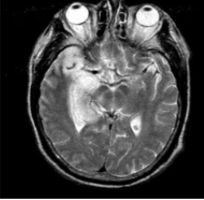

Ax = herpes simplex

Ix = LP, EEG (abnormalities), MRI (temporal lobe)

Tx = IV aciclovir